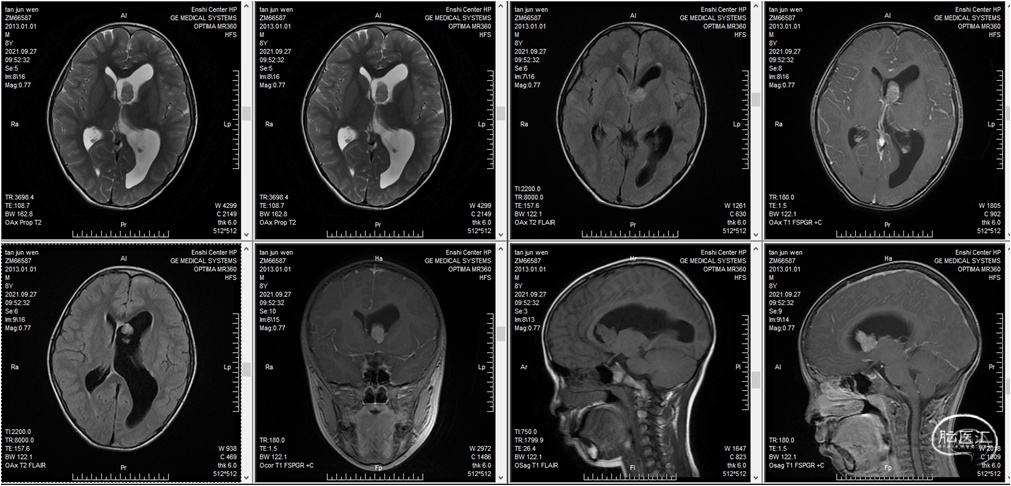

患儿,男,8岁,间断抽搐3次入院,入院核磁提示左侧侧脑室占位。

本例患者以基底节区受累症状为主要表现,但基底节区病灶显示欠佳,活检风险与困难均较大。松果体区为小占位。定位诊断明确,定性困难。如果能通过松果体区病变明确病理,对于基底节区病变的治疗将有较大帮助。如果能通过松果体区病变明确病理,对于基底节区病变的治疗将有较大帮助。因为相对于松果体区与鞍区,基底节区的生殖细胞瘤的治疗更难以评价。

综合考虑上述因素后,决定直接对患者实施开颅手术切除松果体区病灶,手术入路采用枕下后正中入路。该手术方案有以下几点好处:1.切除肿瘤获得组织标本,可以有足够的标本量来明确病理类型,指导后续治疗特别是放射治疗;2.全切除病变,解除导水管梗阻,打通脑脊液循环通路;3.对脑室系统干扰小,有可能降低交通性脑积水发生概率;4.不切开胼胝体,对正常结构损伤小。但是该手术方案也有需注意的地方:1.病变位置深在,周围结构重要,操作空间不大,而病灶较小,术中需小心寻认,以免遗漏,或病变被吸引器误吸不能留到标本;2.幕下入路有发生幕上部位血肿的可能。